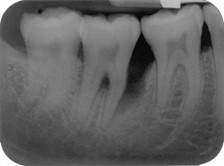

43-year-old man attends your surgery with severe toothache. He admits that he is not a regular attender and knows he has neglected his teeth. Clinical examination reveals many broken restorations and carious cavities. The pain is associated with his lower left second molar (37) which is tender to percussion. from the photo and radiograph list 3 findings that relevant from pt symptoms of 37

* fracutres DB cusp * amalgam restoration encroaching on pulp space * secondary cares (radiolucency) under distal amalgam * slight PDL widening (mesial) and PA radiolucency on mesial root * furcation bone loss (radiolucency)

43-year-old man attends your surgery with severe toothache. He admits that he is not a regular attender and knows he has neglected his teeth. Clinical examination reveals many broken restorations and carious cavities. The pain is associated with his lower left second molar (37) which is tender to percussion. periapical dx

acute apical abscess inflammatory reaction to pulpal infection and necrosis, characterised by rapid onset, spontaneous pain, TTP, pus and swelling of associated tissues